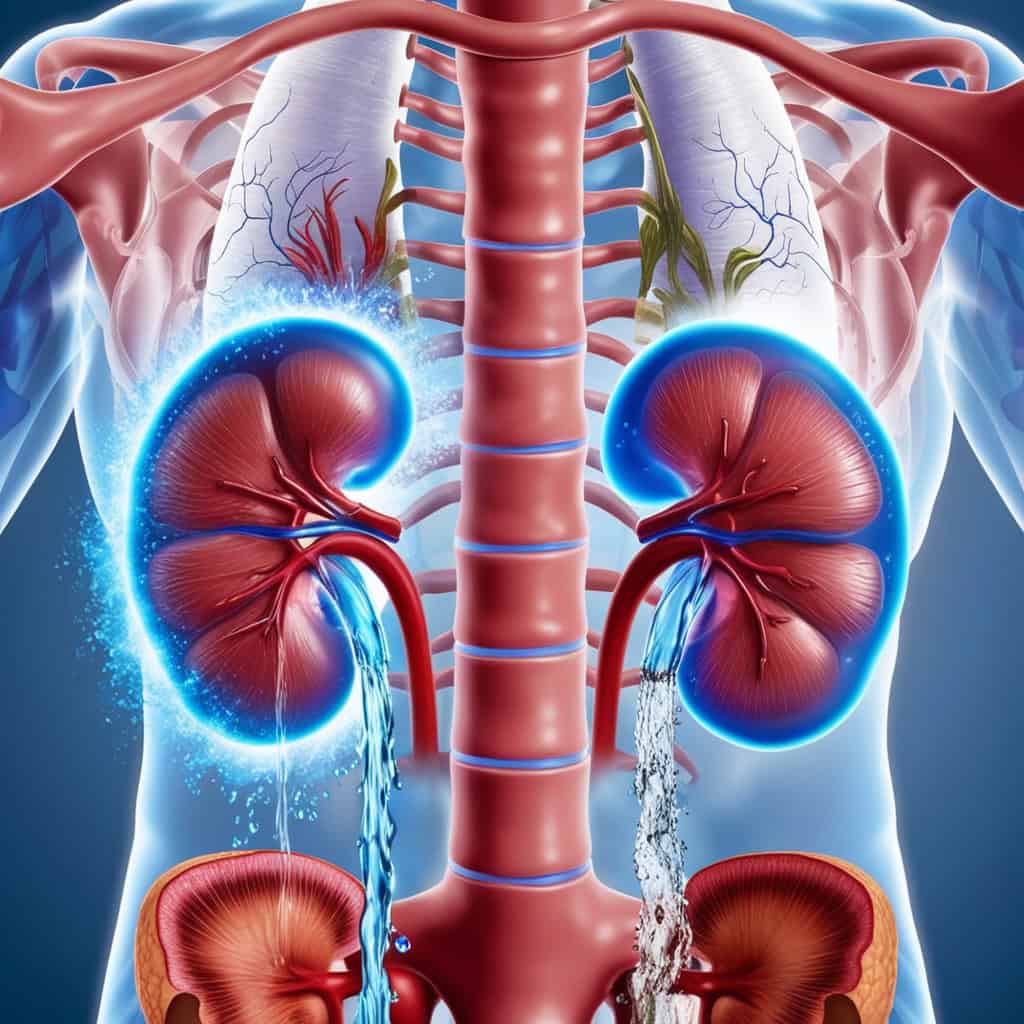

(3) Membantu Buah Pinggang Menyingkirkan Toksin

Buah pinggang kita bekerja 24 jam sehari untuk menapis darah dan membuang sisa toksin melalui air kencing. Tapi kalau kita kurang minum air kosong, kepekatan toksin dalam badan akan meningkat dan boleh menyebabkan batu karang serta masalah buah pinggang. Minum air yang cukup memastikan sistem perkumuhan kita berfungsi dengan baik dan mencegah penyakit berkaitan buah pinggang.

(1) Membebankan Buah Pinggang

Buah pinggang kita hanya boleh menapis air dalam jumlah tertentu pada satu masa. Bila kita minum air kosong berlebihan, buah pinggang terpaksa bekerja lebih keras untuk mengeluarkan lebihan cecair. Jika dibiarkan berterusan, ini boleh meningkatkan risiko kegagalan buah pinggang dalam jangka panjang.